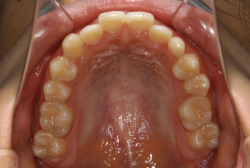

ネックバンドを1年半使用して、上顎大臼歯が十分後ろに下がったところで、裏側にリンガルアーチという固定のワイヤーを取り付けて、新しく生じた隙間が狭くならないよう「保隙(ほげき)」という処置をして、永久歯が生えそろうまで待機中の様子です。配列全体に隙間が生じているのがお分かりいただけると思います。これだけの隙間が確保できていれば、抜歯をしなくても、あとで上の前歯を内側に理想的な角度で引っ込めることができます。このように完全に永久歯列になる前に、十分な隙間が確保できるかどうかが、非抜歯で矯正できるかどうかの分かれ目になります。